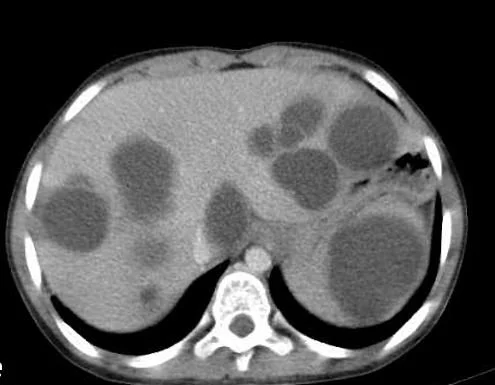

Our patient had amebic liver abscesses.

Entamoeba histolytic is a parasitic protozoan transmitted  by ingesting water contaminated with feces. It is estimated that It  affects 12% of the world’s population with 90% of infections being asymptomatic .  While many people are asymptomatic, others develop fever, diarrhea and abdominal pain. Two stages of the organism are present: the cystic stage and the infective or trophozoite stage. The cysts are ingested in contaminated water and in most people the trophozoites that develop in the intestine are shed in the feces.  In others, the trophozoites  penetrate the intestinal wall into blood vessels and travel through the portal circulation to the liver  where abscesses form.  Amebic abscesses have been reported in other organs including the brain, kidneys and heart but the liver is the most common.

The disease is most common in men from 18-40 and ten times more likely in men than women. Symptoms usually occur in 2 to 4 weeks after exposure in an endemic region although there are reports of delayed presentations months to years after exposure. The genetic background plays a role in the development of abscesses.. The Mexican mestizo population is at risk for development of amebic liver abscesses .because of the presence of  LA-Bwl6 and HLA-DRB3 alleles.

the fluid removed from an amebic abscess is described as anchovy paste.

Only 10% are diagnosed on stool examination while serologic testing is 95% sensitive with indirect hemagglutination (IHA) or ELISA.

Treatment is with metronidazole 500 to 50 tid for ten days followed by paromomycin. Aspiration is needed if the lesion is five cm or greater. Surgery is generally required for lesions that rupture.

Our patient was treated with pigtail catheters placed into the lesions and was given metronidazole.  He recovered successfully.